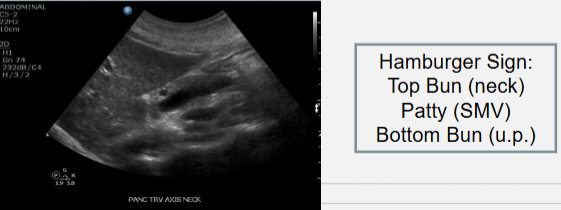

Trv Pancreas Neck- uncinate process and SMV (hamburger)